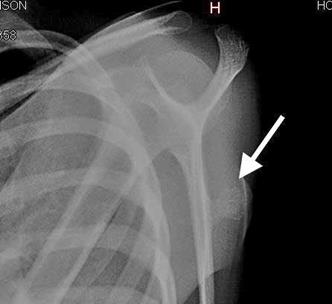

En analíticas de laboratorio, se reportaron valores dentro de parámetros normales, se corroboró la existencia de adecuada función renal y tiempos de coagulación que nos da evidencia del buen funcionamiento orgánico previo a la cirugía y por tanto de resultados favorables y menor riesgo de complicaciones. Se solicitaron estudios imagenológicos: radiografía en Y escapular evidenciando radio opacidad ósea a nivel de tercio proximal de escápula. (Figura 2)

Figura 2: Radio opacidad en miembro superior izquierdo con densidad ósea.